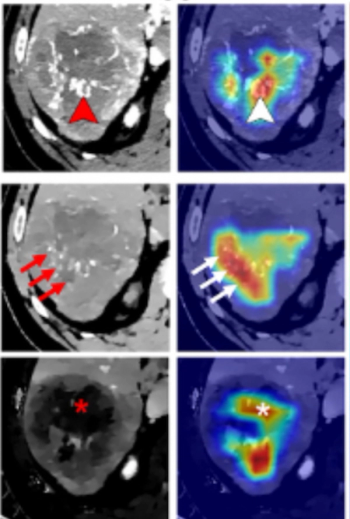

Reportedly offering improved delineation of pulmonary structures and greater accuracy with computed tomography (CT) values of pulmonary tissue, the artificial intelligence (AI)-powered LungQ 3.0.0. may facilitate enhanced precision and efficiency with interventional procedures such as lung volume reduction and ablation procedures.